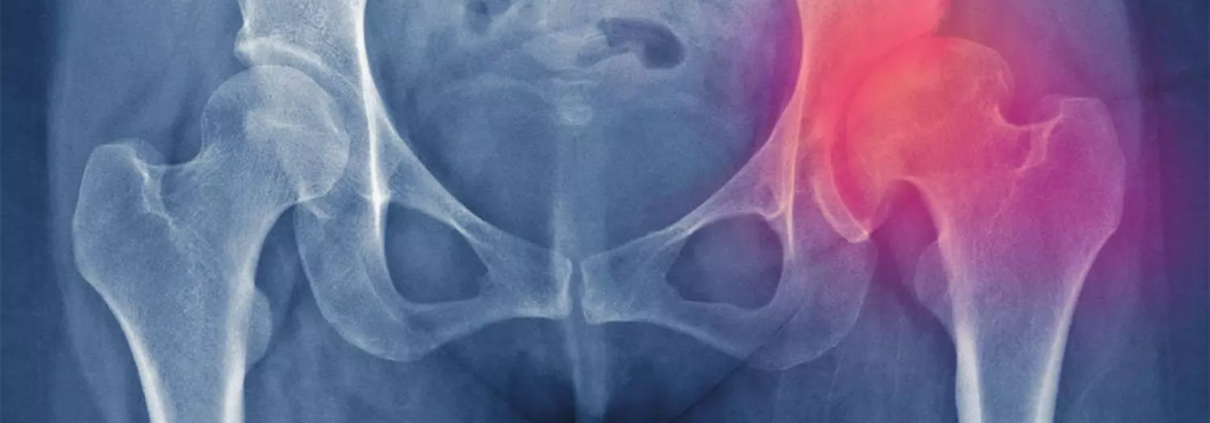

Acetabular Dysplasia Linked to Increased Risk of Hip Osteoarthritis in Women and Older Adults: Research Suggests

Hip osteoarthritis (OA) has no curative nonsurgical treatment, making prevention vital. However, understanding risk factors for radiographic hip OA (RHOA) remains limited. Subtle hip shape abnormalities, such as acetabular dysplasia, may precede OA development and represent potential targets for prevention. AD, characterized by insufficient coverage of the femoral head by the acetabulum, leads to mechanical cartilage stress and may contribute to OA progression. Previous studies suggest an association between AD and RHOA, but inconsistencies and limited statistical power have hindered conclusive evidence.